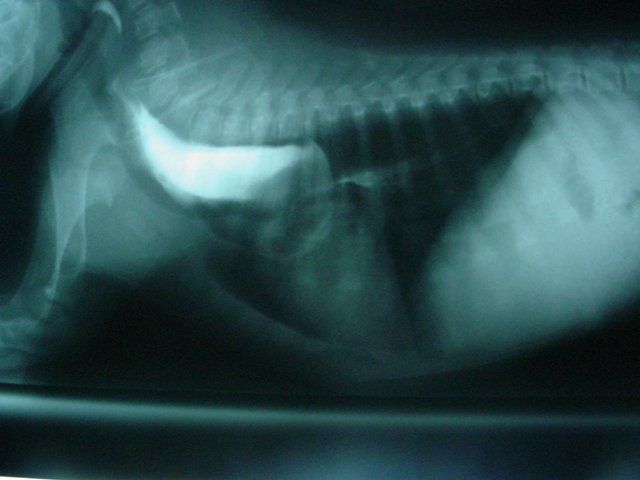

The x-ray below is one of the films taken with barium. Barium is a contrast media that can be used to outline hollow structures since it is bright white on x-rays. The x-ray on the left shows barium in a widened esophagus and a sudden area of narrowing and a lesser amount of barium after the stricture. The stricture occurs at the level of the 5th to 6th rib. In this area, it can be presumed that the stricture is caused by a persistent right aortic arch (PRAA) or vascular ring.